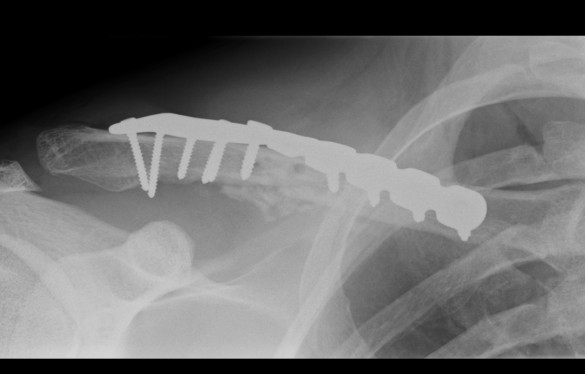

Plate fixation of shorted displaced midshaft clavicle fractures reduces nonunion rates

Operative Management

Plate fixation

Superior versus anteroinferior plates

Nourian et al J Orthop Trauma 2017

- systematic review of superior v anteroinferior plates

- no difference in outcome or union rates

- higher incidence sympomatic hardware with superior plates

Technique

- clean and reduce fracture

- application contoured locking plate

- need 6 cortices each side